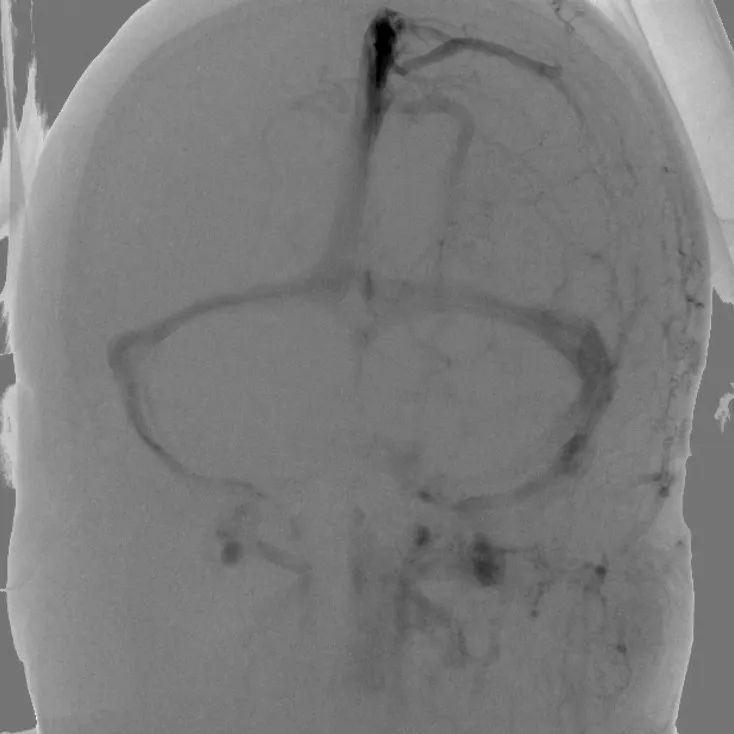

【术前DSA】 【术后DSA】

因颅内静脉血管壁薄,有静脉瓣阻挡,同时血管迂曲、变异度高,其手术难度高、风险大、手术时间长,极其考验术者的技术、耐心和毅力。在麻醉科的全力保障和神经内科团队的不懈努力下,取出大量血栓,大脑静脉血流重新恢复,手术历时约3小时。术后患者头痛症状缓解,一周后康复出院。